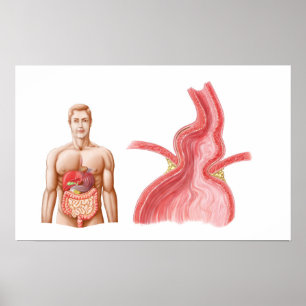

Medical Ilustration Of A Hiatal Hernia In The Poster

PriceCA$50.75